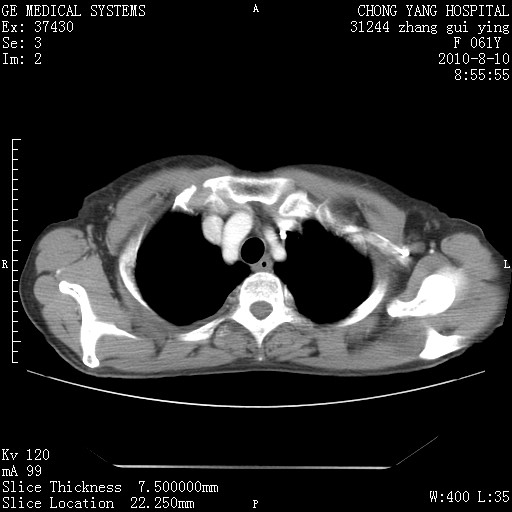

标题: CT28314:F61Y胸部增强,发热咳嗽一周入院,后面的为一周前平 [打印本页]

标题: CT28314:F61Y胸部增强,发热咳嗽一周入院,后面的为一周前平

1、支持考虑右侧中央型肺癌伴右肺中叶节段性不张及下叶支气管黏液痰栓    2、左肺上叶舌段感染。

支持右下肺中央型肺癌并左上肺感染.

支持3楼意见,还要考虑:纵隔及肺门淋巴结转移、右侧少量胸腔积液。

确切的说:1:右肺下叶中心型肺癌侵及中叶支气管并中叶不张,纵膈淋巴结转移。2:左肺舌叶炎症。3:右侧胸腔少量积液

块影平扫32hu,动静脉期62-70hu.

1:右肺下叶中心型肺癌侵及中叶支气管并中叶不张,纵膈淋巴结转移。2:左肺舌叶炎症。3:右侧胸腔少量积液。支持!

右肺下叶内基底段近膈不规则肿块,考虑右肺下叶周围型肺癌可能性大。

右肺下叶中心型肺癌侵及中叶支气管并中叶不张,纵膈淋巴结转移。2:左肺舌叶炎症。3:右侧胸腔少量积液